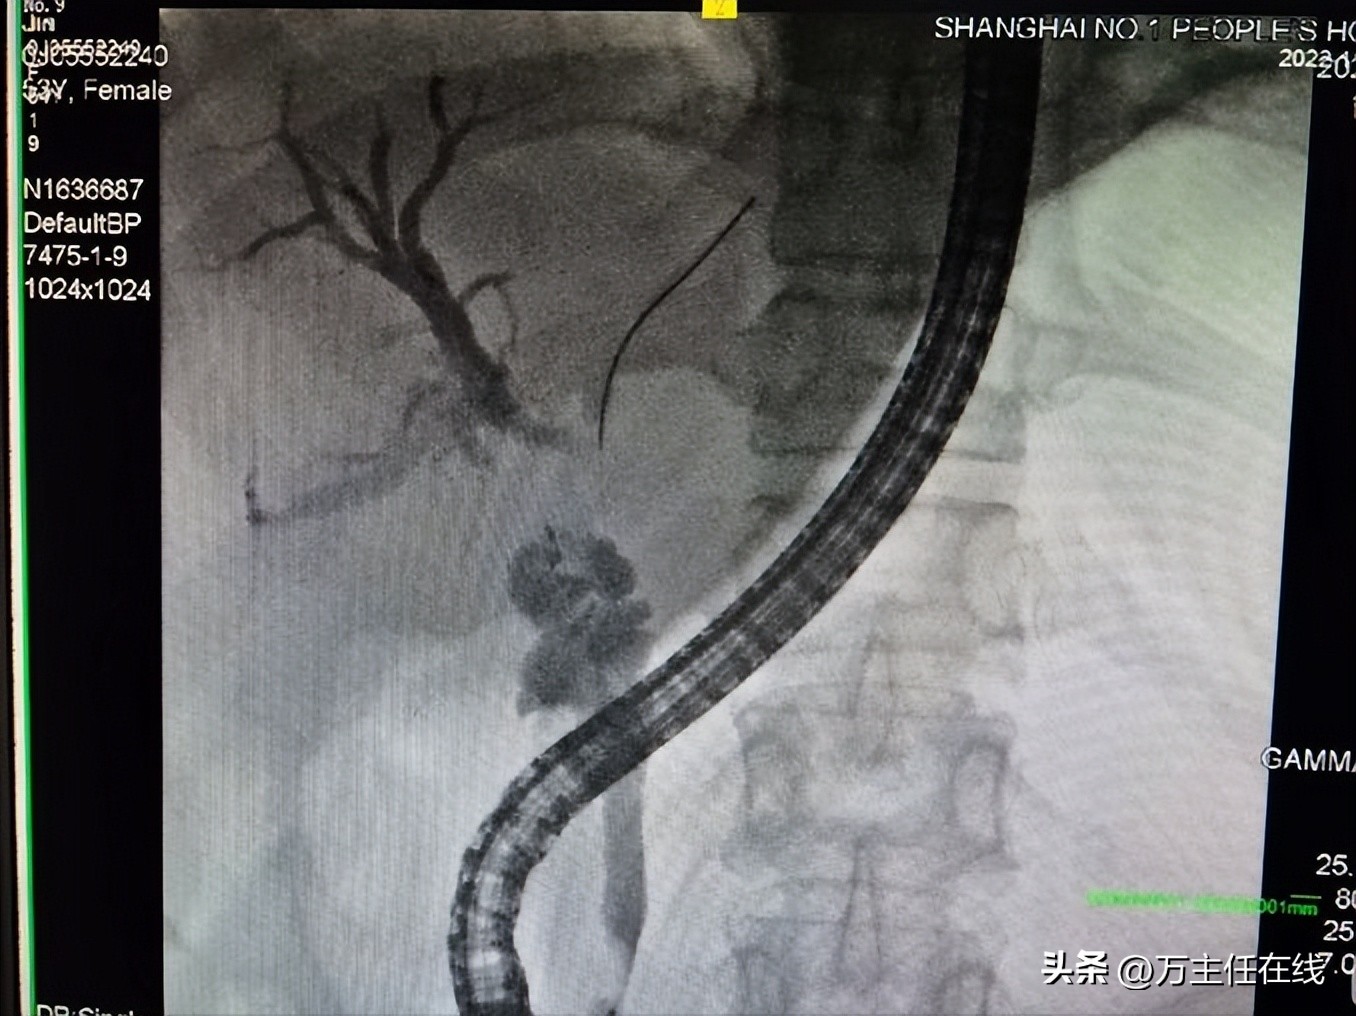

胆道造影

Spyglass引导下导丝置入胆囊内